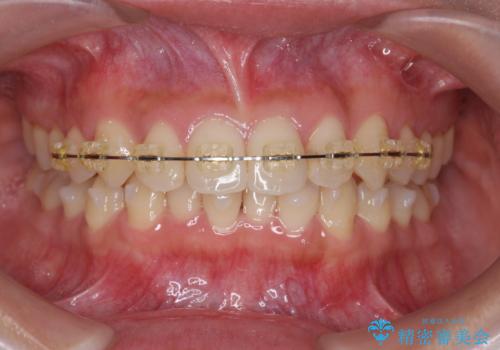

ワイヤー部分矯正治療を併用したマウスピース矯正治療

- 前歯のねじれ、深い噛み合わせ(ディープバイト)の改善を求めて来院されました。

マウスピースでは改善の難しい、歯のねじれ・ディープバイトを部分ワイヤー矯正で改善したのち、マウスピース矯正で全体の歯並びを整えていきます。

部分ワイヤー矯正を行ったことで前歯をしっかりと綺麗な歯並びへと導くことができました。